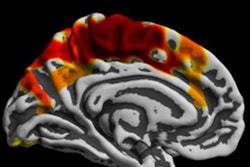

"We observed that higher gray-matter volume in bilateral caudate nucleus and in left cerebellum at age 14 years was associated with a stronger increase in alcohol use scores," wrote the researchers, led by Simone Kühn, PhD, professor of neural plasticity at the University Medical Center Hamburg-Eppendorf in Germany. "This finding fits well to previous studies pointing at an association between increases in striatum and psychiatric disease."

The MR images showed that teens with more gray matter in the caudate nucleus, which is associated with learning, and the left cerebellum, which handles thinking and movement, were more likely to increase their drinking habits over time.